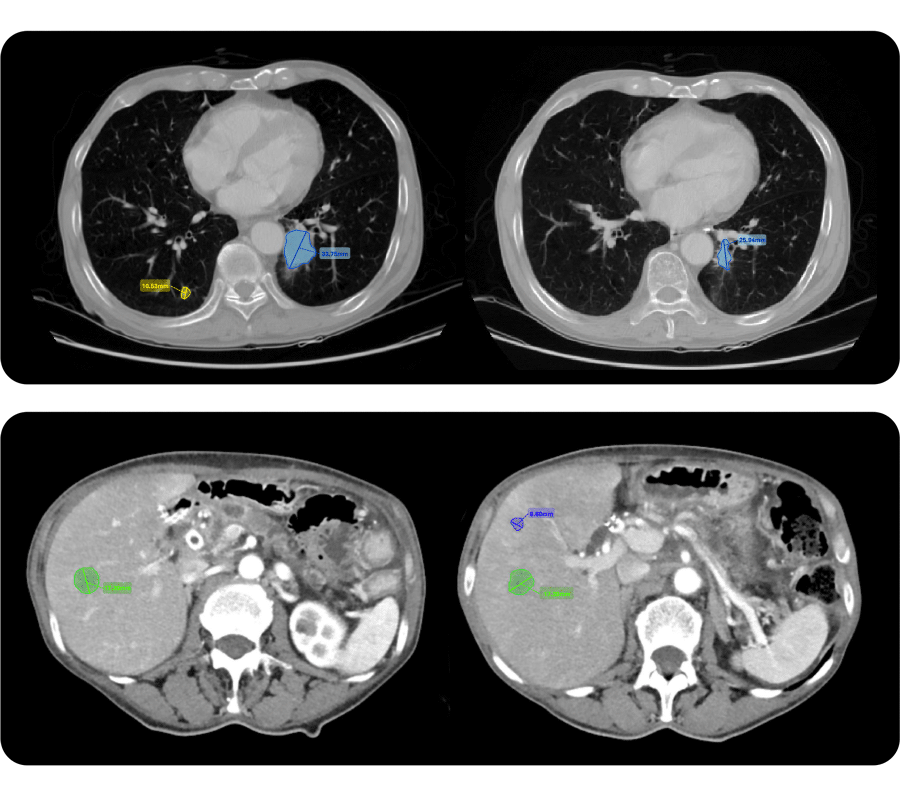

1. AI-supported lesion-assessment tool

Automatically detected, segmented, and measured target lesions of a patient with advanced NSCLC at baseline [left] and 1st on-treatment scans [right]

Quibim’s tools automatically identify, segment, measure, and track lesions throughout the clinical trial. By streamlining these processes, faster and less variable radiological assessments are enhanced to achieve more consistent interpretations. Experts can also manually segment or adjust automated results within an integrated DICOM viewer, supporting RECIST 1.1 and its variations without compromising workflow efficiency.